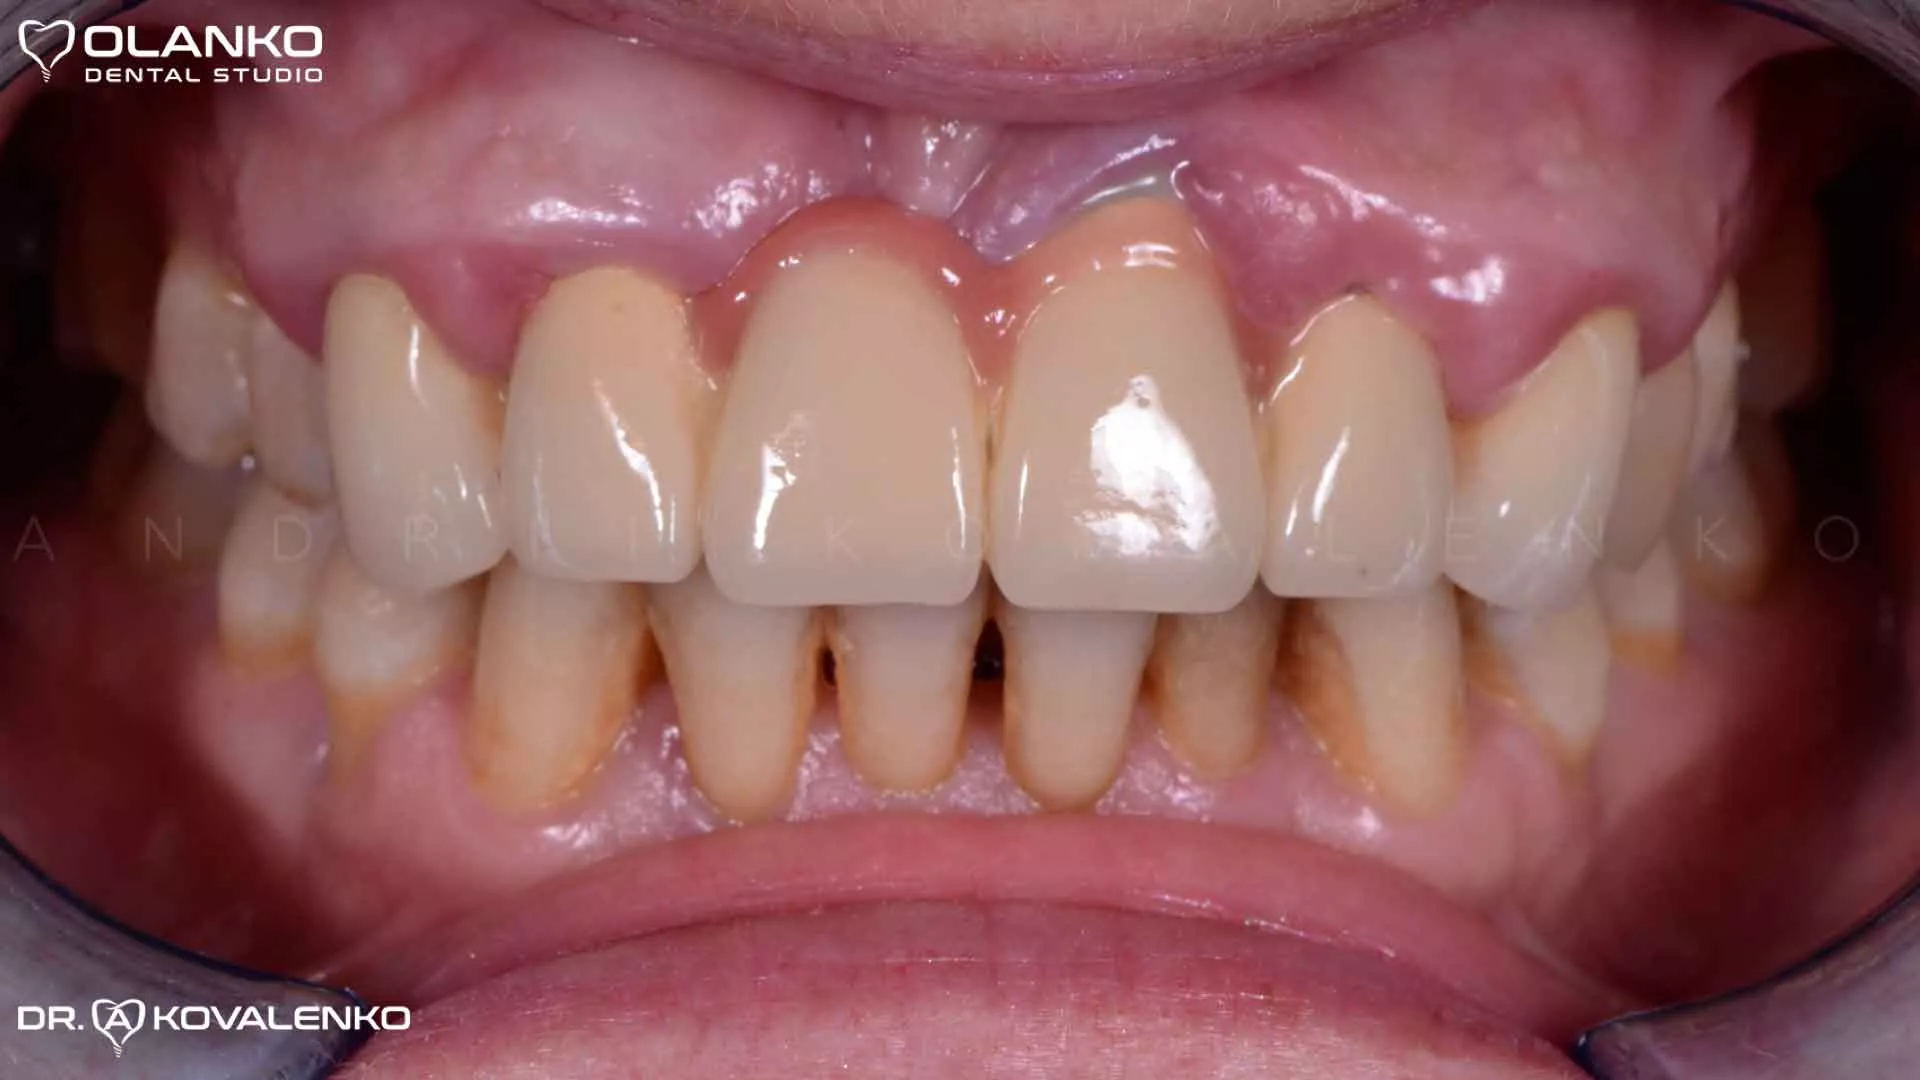

Фото вигляд зруйнованих зубів після зняття металокерамічного мосту